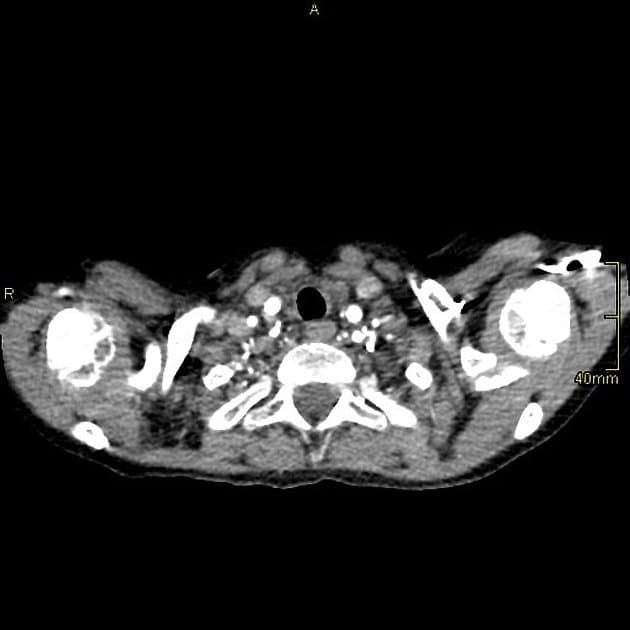

CT và MRI

Cho phép trực tiếp quan sát dị tật và thường thấy sự phân tách bằng mô mỡ và/hoặc mô cơ giữa tâm nhĩ phải và thất phải. Chụp MRI cine có thể cung cấp thêm thông tin chức năng ngoài giải phẫu.